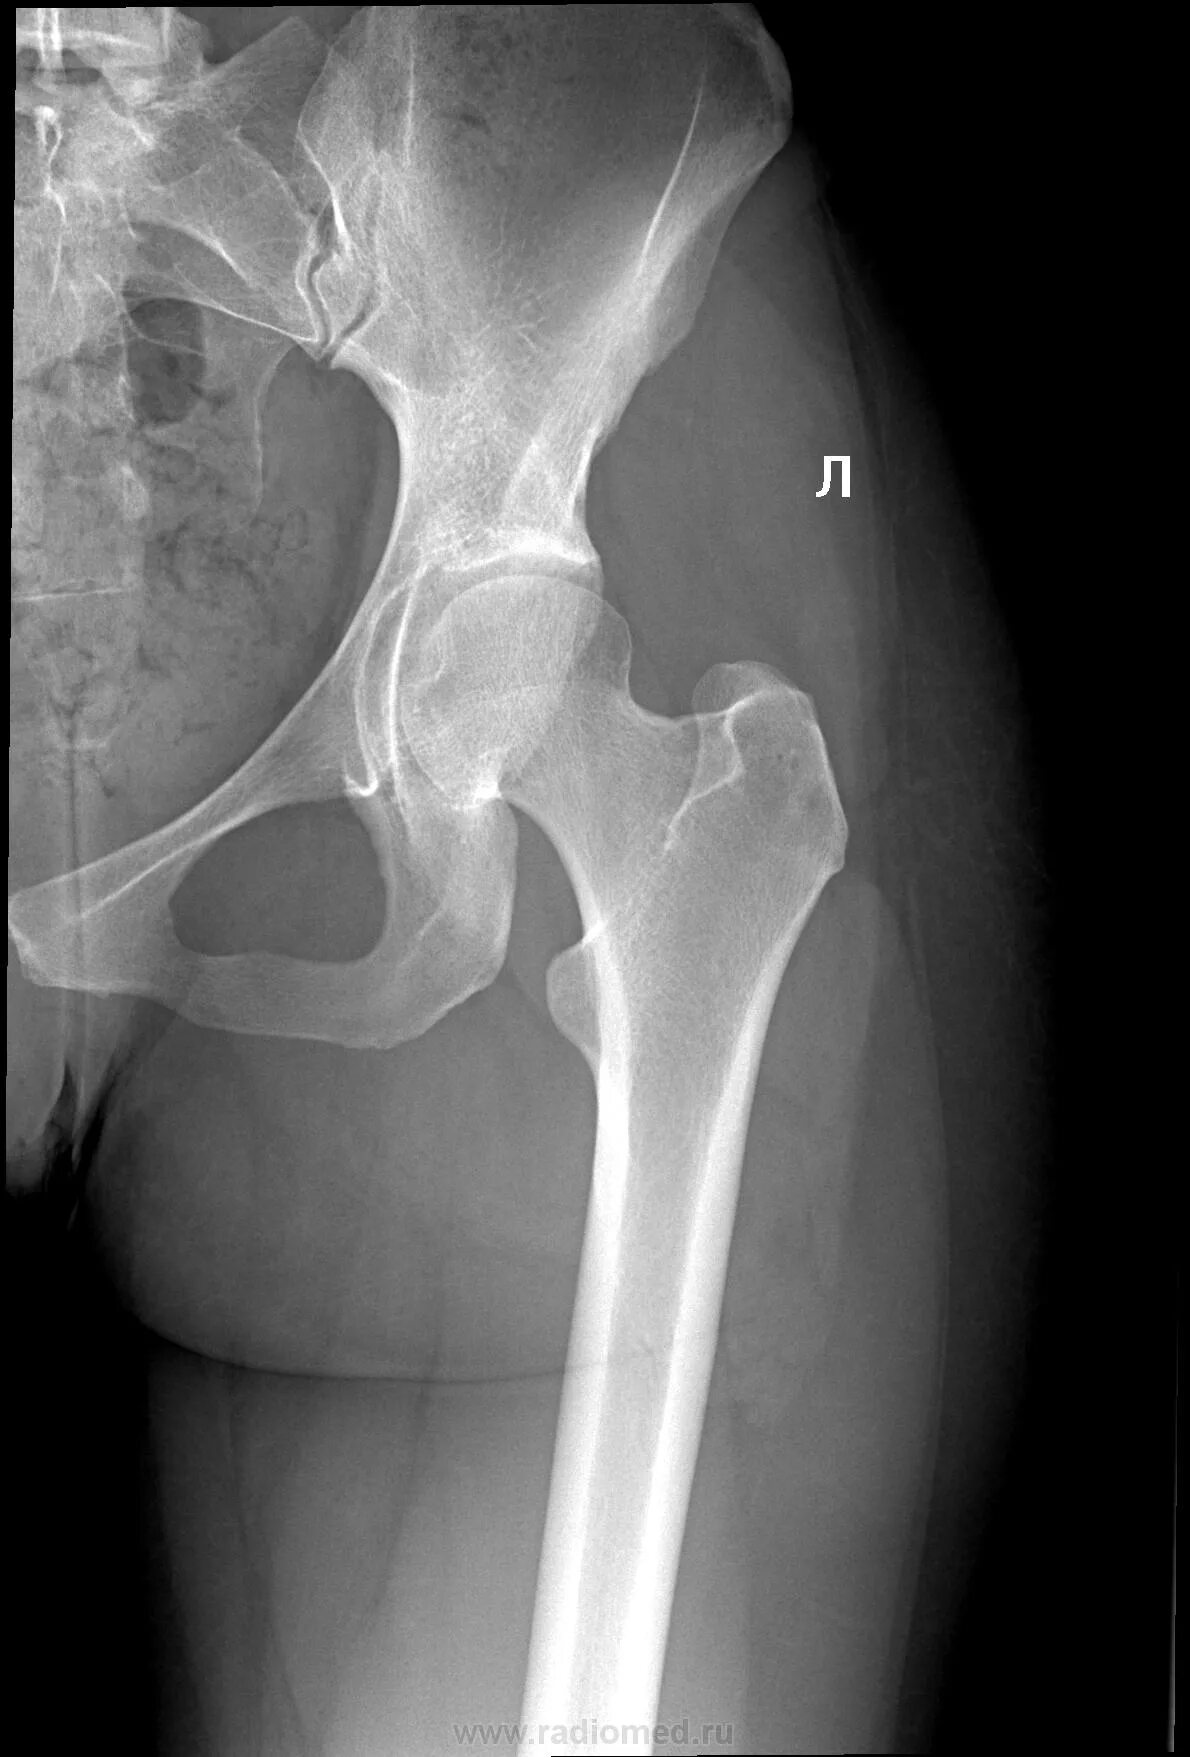

Тазобедренный сустав это